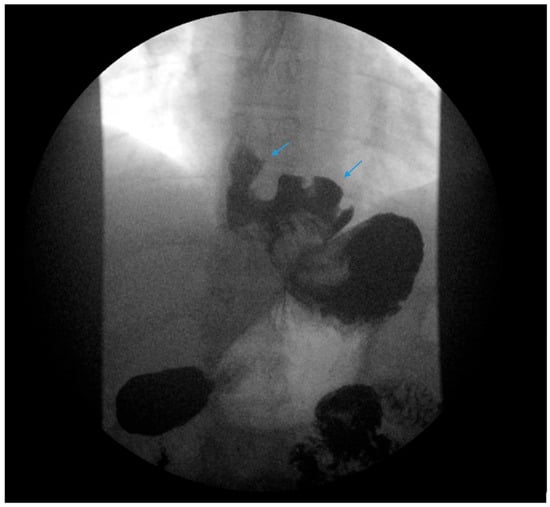

Figure 1.

Upper gastrointestinal series in a patient post-sleeve gastrectomy with early satiety and reflux reveals the following: a small, hiatal hernia and gastroesophageal reflux (blue arrow, left) in addition to abnormal angulation (blue arrow, right) and dilation of the gastric sleeve (green arrow, right). The patient underwent conversion to Roux-en-Y gastric bypass with marked clinical improvement.

An upper gastrointestinal series reveals a moderate, sliding type-one hiatal hernia (bottom arrow) in addition to gastroesophageal reflux disease (top arrow) in a patient with morbid obesity.

Complications of SG, including stenosis, angulation or kinking, are associated with increased intragastric pressure and GERD (Figure 1) [38]. Data regarding the optimal bougie size for weight loss and reduced reflux are mixed, but generally support a range of 36–42 French [39,40,41,42,43]. Overfilling of the gastric sleeve due to a large meal portion may result in reflux symptoms, and thus, patients should be counseled to gradually advance their diet from liquids to small portions of healthy, protein-rich foods. The gastric sleeve dimensions should be sufficient, as too narrow of a gastric sleeve may result in increased intragastric pressure and subsequent reflux. An abnormally narrow sleeve may also lead to regurgitation due to overfilling, even in patients with a competent lower esophageal sphincter and no hiatal hernia. Felinska et al. described the ideal shape of a gastric sleeve to be a trapezoid with a wide antrum and a narrow cardia to prevent sleeve stenosis or increased pressure within the stomach [34]. Furthermore, the preservation of the antrum has been suggested to increase gastric emptying and reduce subsequent GERD [44]. Esophagogastric dysmotility may be a contributing factor to post-SG GERD and a dynamic contrast study can be a useful test in establishing the diagnosis.